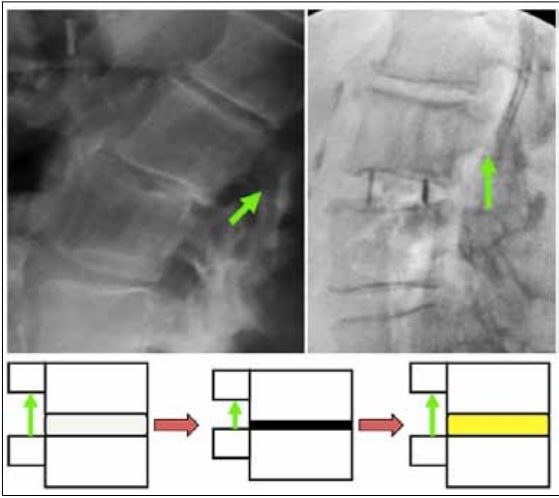

La descompresión indirecta es un enfoque quirúrgico que se basa en recuperar la altura del disco intervertebral sin tener que actuar los elementos posteriores de la vértebra. Al aumentar la altura del disco intervertebral conseguimos aumentar los diámetros del canal espinal. Con una descompresión indirecta podemos llegar a aumentar la altura del disco que puede pasar de 3 a 5 mm lo que provoca que la sección del canal pase de 136mm2 a 159 mm2 al año de la intervención . Con la descompresión indirecta también se produce un aumento de la sección de los agujeros por los que salen las raíces nerviosas. El foramen derecho pasa de 91 mm2 a 113mm2 y el izquierdo de 87mm2 a 114mm2. Además con la descompresión indirecta es posible recuperar de una manera más eficiente la lordosis lumbar

La descompresión indirecta se puede lograr mediante diferentes técnicas quirúrgicas. Principalmente se utilizan vías anteriores y laterales que son las que permiten aumentar la altura del disco intervertebral de una manera eficaz. Las vías de abordaje anteriores y laterales son más anatómicas y permiten recuperaciones más precoces. En ocasiones a una técnica anterior se asocia la fijación con tornillos percutáneos posteriores, pero si realizamos una descompresión indirecta no deberíamos desinsertar la musculatura de la espalda ni actuar sobre las articulaciones facetarias. Abordajes como el ALIF, LLIF o OLIF son utilizados para realizar descompresiones indirectas. (Anterior, Lateral, Oblique lateral interbody fusion)